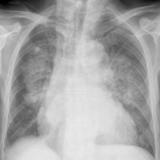

APE 1

Date: 11/05/2005

Views: 4196